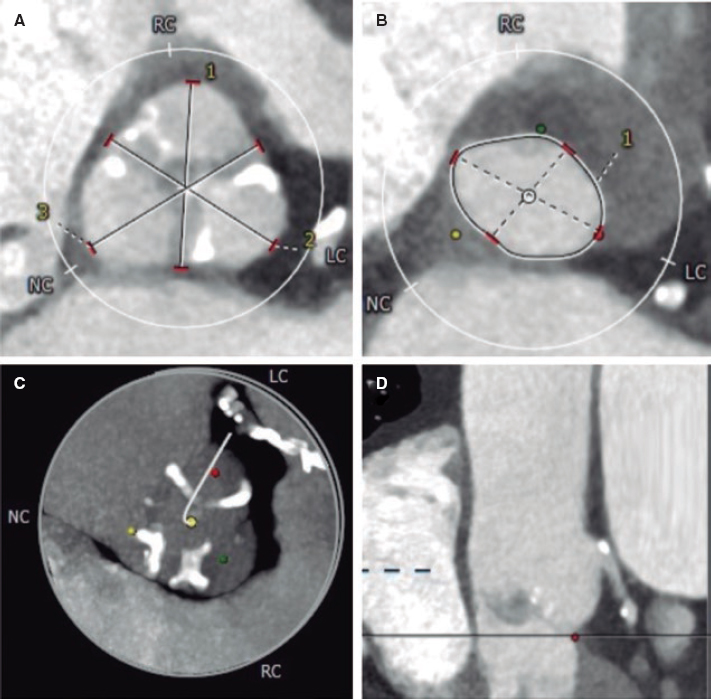

Regarding the procedure, it should be noted that the crossing rate for the ICL balloon was 100% despite a high percentage of plaque preparation was required (62% balloon pre-dilatation, 27% rotational atherectomy). Recently, the combination of rotational atherectomy and ICL has been described as RotaTripsy, suggestive that these 2 calcium debulking techniques may be complementary, since rotational atherectomy facilitates the ICL balloon crossing, and the latter facilitates proper expansion in the presence of circumferential deep calcium plaques.9 The device success rate was 84% (100% in the Disrupt CAD II linical trial) and the clinical success rate was 95% (94% in the Disrupt CAD II trial). And most important of all, no major procedural complications were seen, which is consistent with the Disrupt CAD II trial results. The rupture of the ICL balloon during inflation occurred in 3 cases (12%) without associated complications, yet the rupture of the balloon has been described in a case report resulting in a type C coronary dissection; the interventional cardiologist needs to be aware of this lithotripsy-related potential complication.10 Intravascular imaging were performed in few cases probably because the operator thought it would be difficult to cross an especially severe and calcified lesion with the OCT or IVUS catheter. Consistent with the results of the Disrupt CAD I and II clinical trials and OCT substudy,5,11 it was confirmed that the modification of calcium and the presence of fractures lead to an acute area gain and favorable stent expansion in the lesions assessed through OCT in our series. Figure 1 shows the coronary angiography and OCT of one complex patient treated with ICL; the red arrows seen on figure 1D,E indicate calcium fractures after the ICL.

Figure 1. Intracoronary lithotripsy, angiography, and optical coherence tomography. Patient with severe coronary artery heart disease with severely depressed left ventricular ejection fraction previously treated with coronary artery bypass graft (venous graft-left anterior descending coronary artery, currently occluded). Treatment of left main coronary artery, left anterior descending artery, and diagonal branches. A: pre-intracoronary lithotripsy angiography. B: Impella-assisted PCI of left anterior descending coronary artery. Arrow indicates inflated lithotripsy balloon. C: successful final angiographic result after stenting. D, E and F: optical coherence tomography cross-sectional images of a post-lithotripsy calcified lesion. Red arrows indicate calcium microfractures after intracoronary lithotripsy.